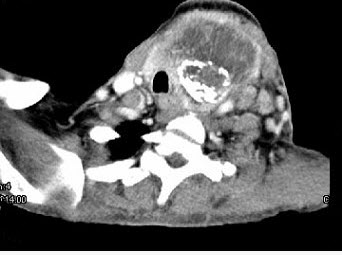

- 单项选择题女,64岁,发现双甲状腺肿大一月余,CT如图所示,最可能诊断为()。

A、结节性甲状腺肿

B、甲状腺腺瘤

C、甲状腺癌并淋巴结转移

D、甲状腺转移癌

E、甲状腺结核

- C